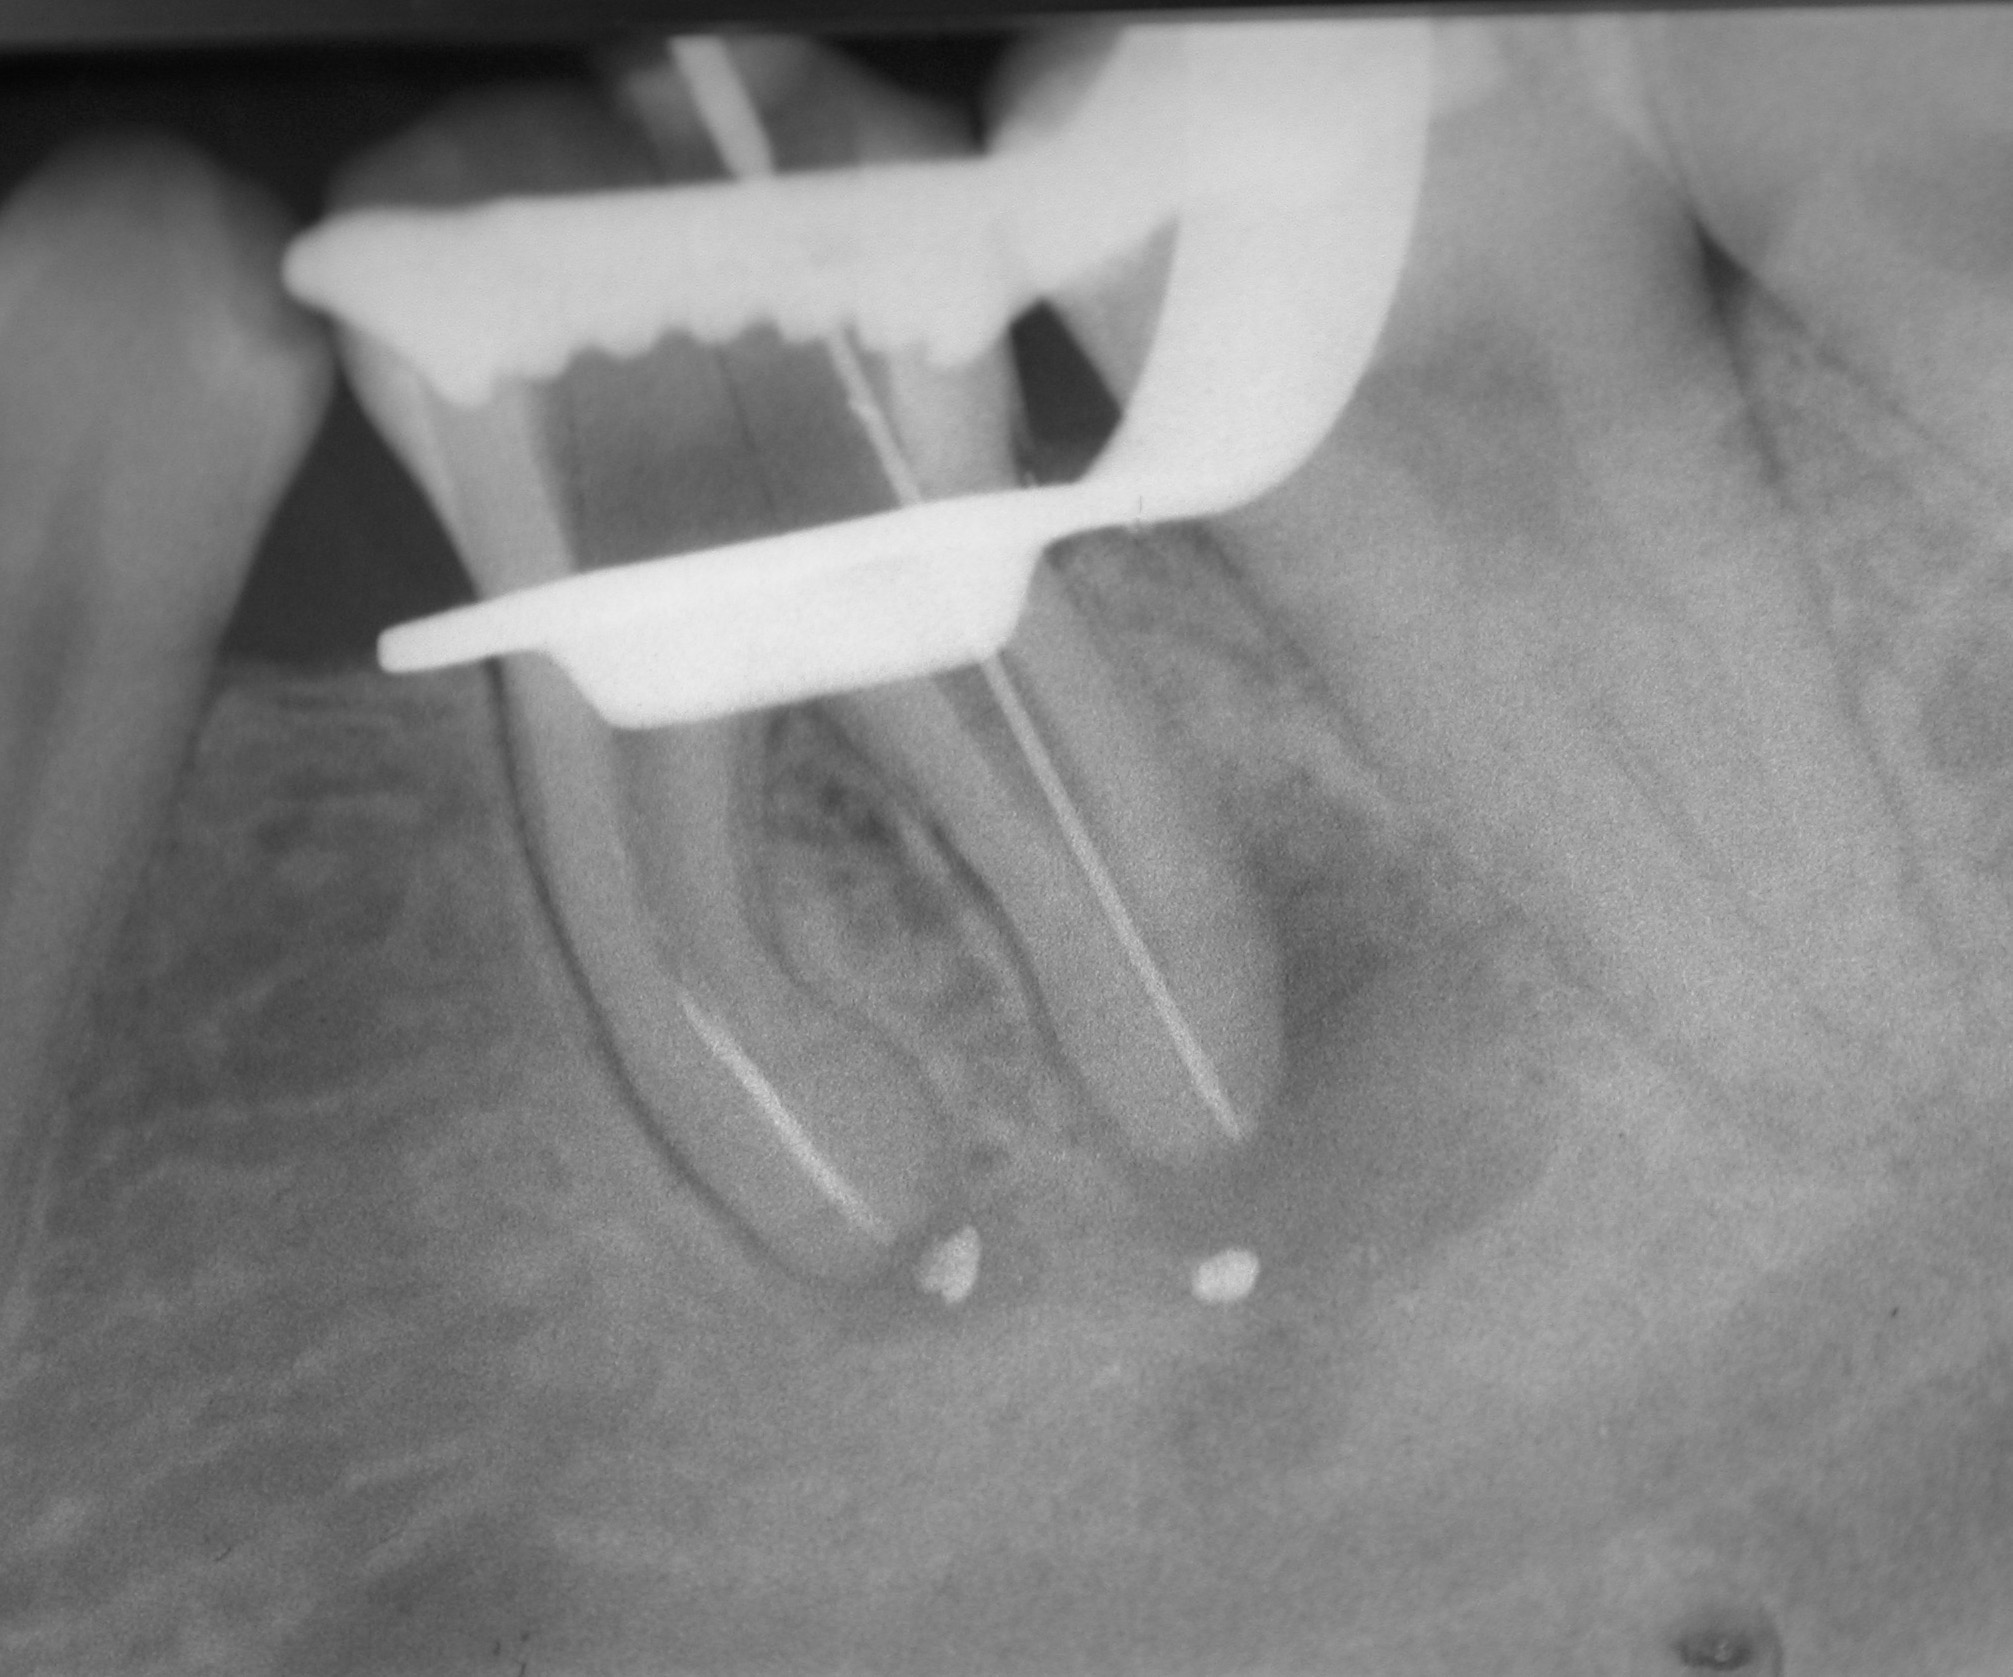

Fast 15 Jahre im Recall – Zahn 36 (2)